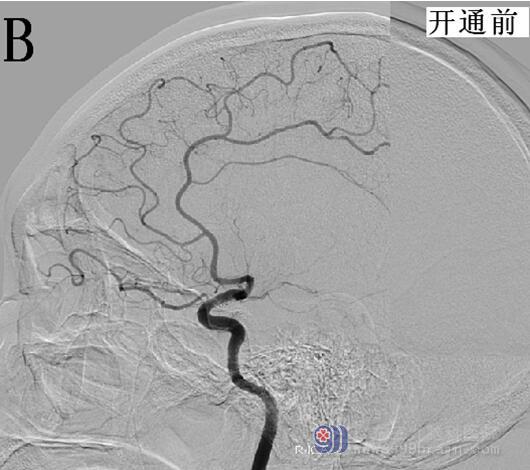

结合患者病史及查体评估,具有静脉溶栓指征,无禁忌症。请示王展航科主任后建议rt-PA静脉溶栓治疗,溶栓后桥接脑血管造影评估血管情况。告知患者家属病情,家属知情并同意溶栓及介入治疗。19:48开始使用rt-PA(50mg),15分钟后患者症状改善,左下肢肌力3+级,双侧眼球左侧活动稍受限,双眼右向凝视,构音欠清,左侧肢体肌力0级,右侧肢体肌力5级,伸舌左偏,左下肢病理征(+),NIHSS评分10分。20:15推入DSA室,行脑血管造影显示右侧大脑中动脉仍存在闭塞,立即桥接取栓+支架置入治疗,约22:30手术结束,术后大脑中动脉上干开通,血流速度恢复,大脑中动脉下干远端闭塞,但大脑前动脉可部分代偿,患者安返病房,生命体征平稳,复测患者NIHSS为6分,溶栓及桥接治疗有效(图2)。复查头部CT,明确无再通后出血,维持血压,预防患者再灌注损伤,定期评估患者NIHSS评分,密切关注生命体征,24小时后启动抗血小板治疗。8天后患者病情明显好转,肢体已恢复部分活动,可自行行走,查体仅遗留左侧肢体肌力5-级,余神经科查体无明显阳性体征。NIHSS:2分。请示王展航科主任,可予带药出院,嘱低盐低脂饮食,戒烟戒酒,控制血压。

图2 A、B为开通前的脑血管造影;C、D为脑血管开通后的造影显像